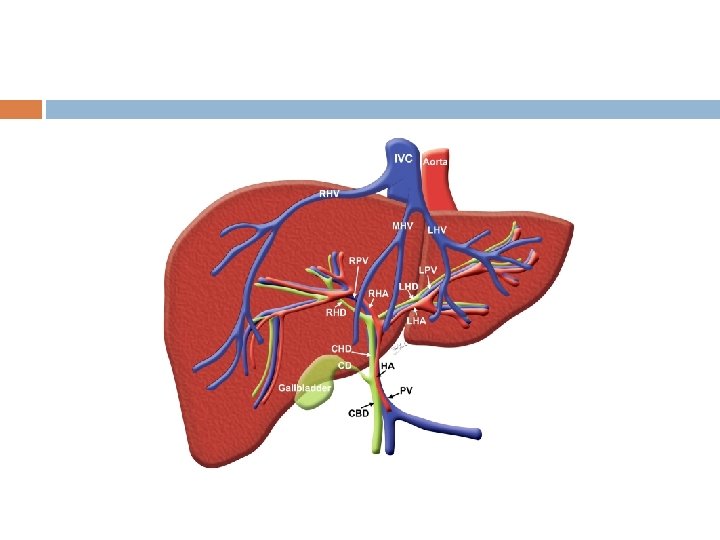

Hepatic Portal System Blood leaving the digestive organs by veins is rich in nutrients…. instead of returning directly to IVC heart this blood is shunted to liver first This way liver can store, convert, detoxify, or excrete materials as necessary Hepatic Portal vein enters liver with nutrient rich blood